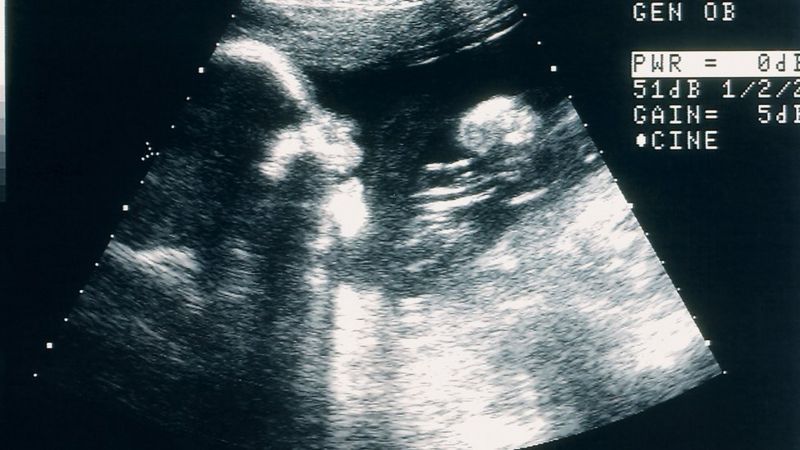

"Había ido al médico por otro tema y cuando le conté que estaba embarazada me hicieron una ecografía. Cuando no encontraron el latido, para mí fue un shock emocional. No había tenido pérdidas, no había ningún indicio de que algo iba mal", dice.